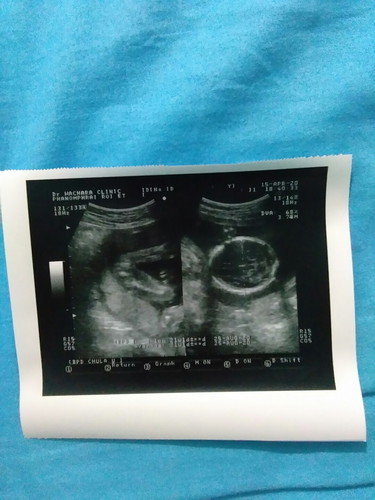

เพศลูก

รบกวนแม่ๆช่วยคอนเฟิร์มให้ทีค่ะ แบบนี้ "หญิง" ชัวร์มั้ยคะ คุณพ่อลุ้นลูกสาวหนักมาก ขอให้สมหวังทีค่ะ #คุณหมอบอก80% แต่อยากได้คอนเฟิร์มจากแม่ๆเพิ่มค่ะ #คุณแม่มือใหม่^^

น่าจะเป็นลูกสาวนะค่ะ บ้านนี้ตอน 17wคุณก็บอกว่าลูกสาว80%ค่ะ ไปตรวจดาวน์ตอน18w คุณหมอบอกล้าน%ลูกสาวค่ะ

จากภาพชัดเจนค่ะ ผู้หญิง แต่ของเราสิ ไม่ชัดเจน แต่หมอก็บอกผู้หญิงค่ะ แต่ไม่เหมือนของคุณแม่เลย

ญ. ค่ะ หว่างขาโล่งๆเหมือนกัน

ญคะ ราบเรียบ ยินดีด้วยจ้า